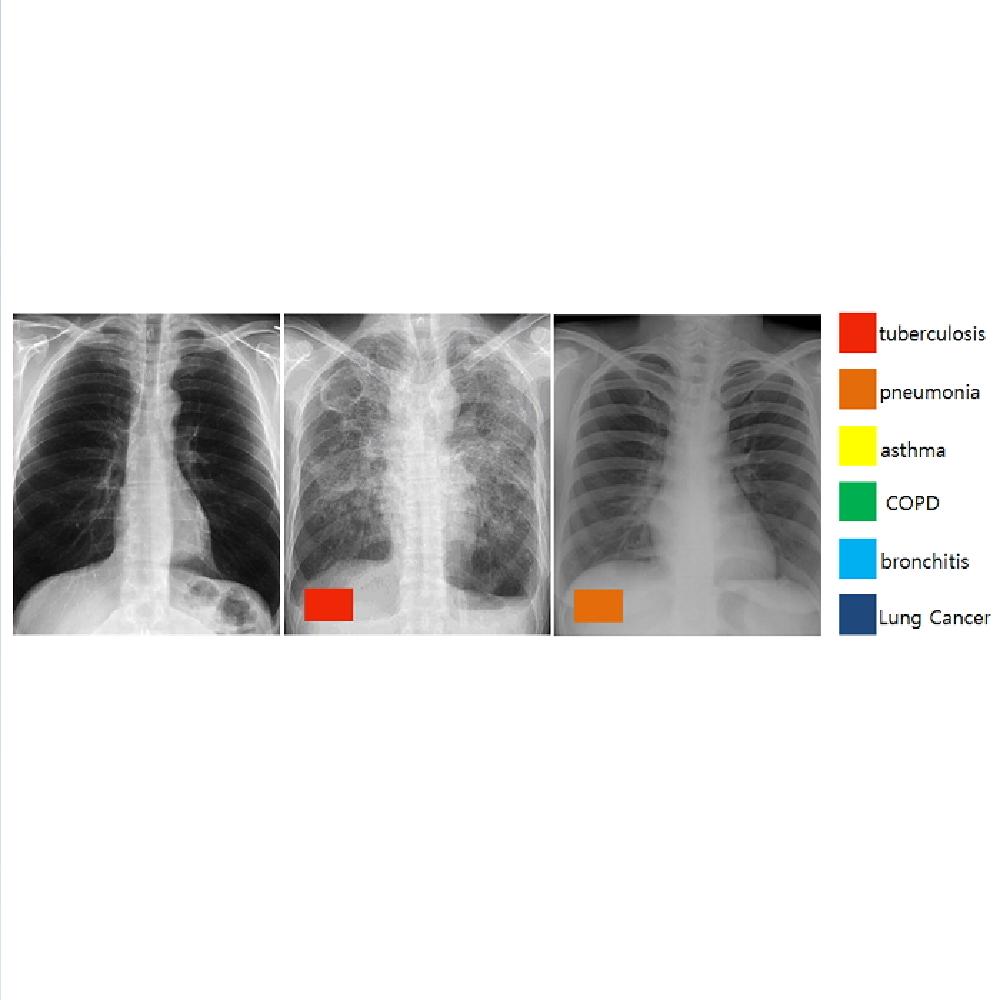

Digital X-ray Radiography Auto decipher

-Based on AI, automagical diagnosis model development for error of DXR-

Need for exact examination of tuberculous (Chest X-Ray)

-Patients have not received exact tuberculous test through chest X-Ray

For tuberculous, the early diagnosis is key

-Need for exact diagnosis of tuberculous, especially where there is no Radionologist